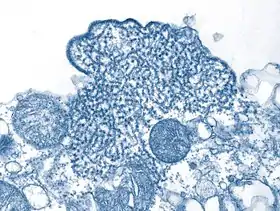

![]() | |

| Електронна мікрофотографія, на якій зображена частинка вірусу Ніпа (фіолетова) під час зараженою культури клітин Vero (коричневий колір) | |